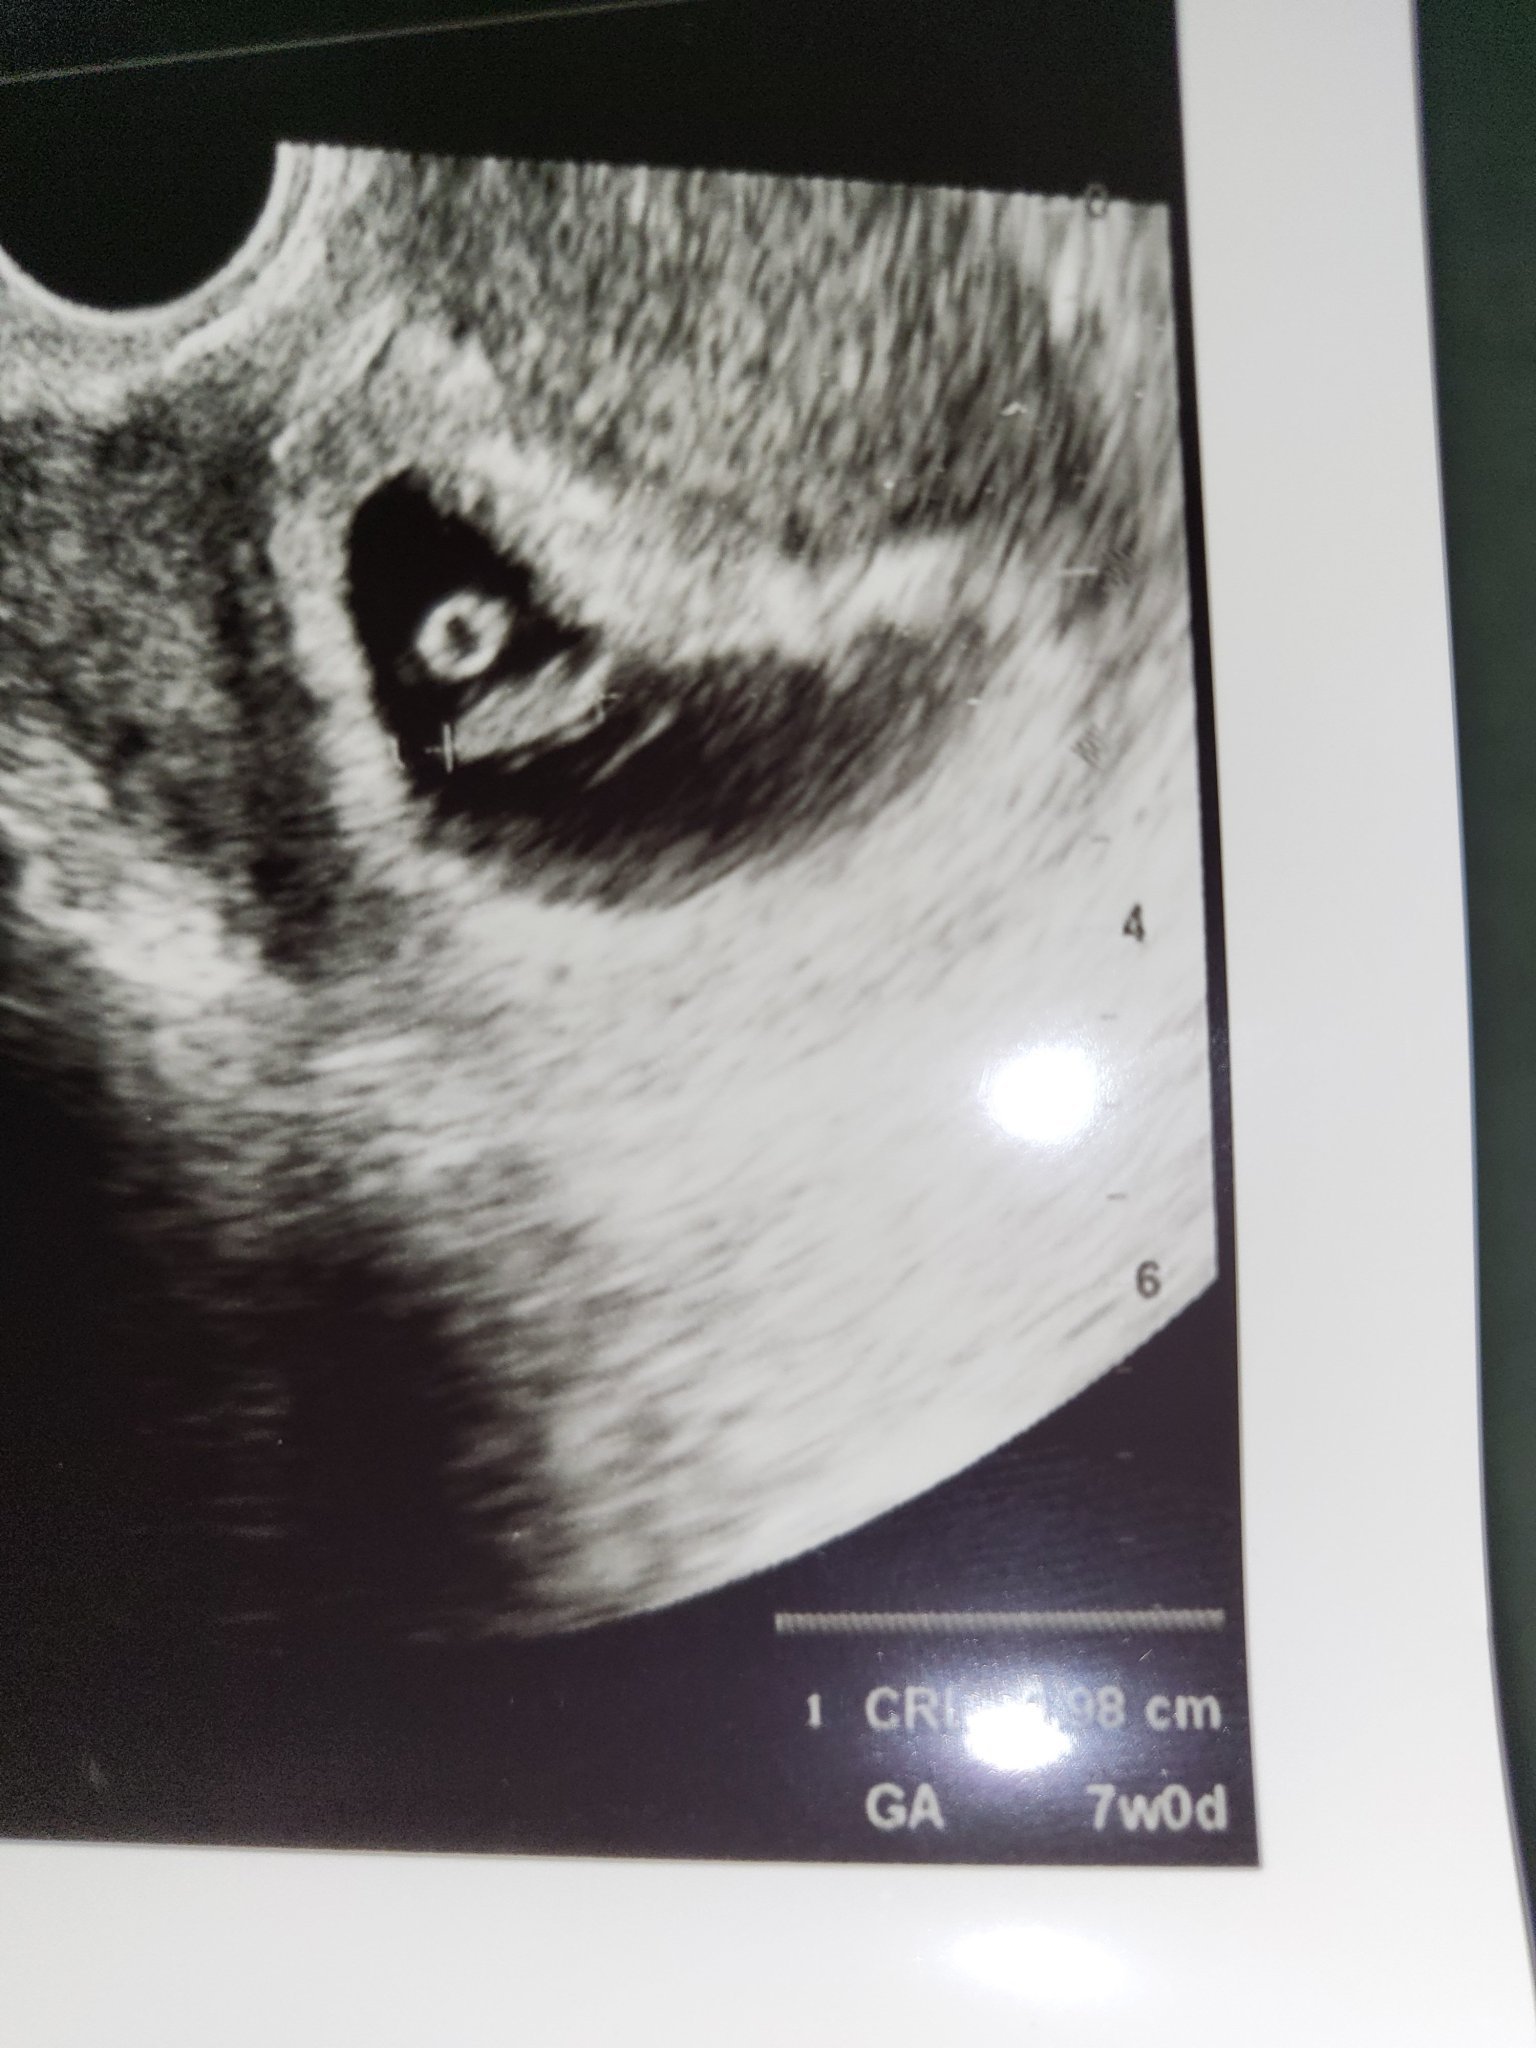

Какво представлява изображението от ехографията на 5-седмична и 2-дневна бременност?